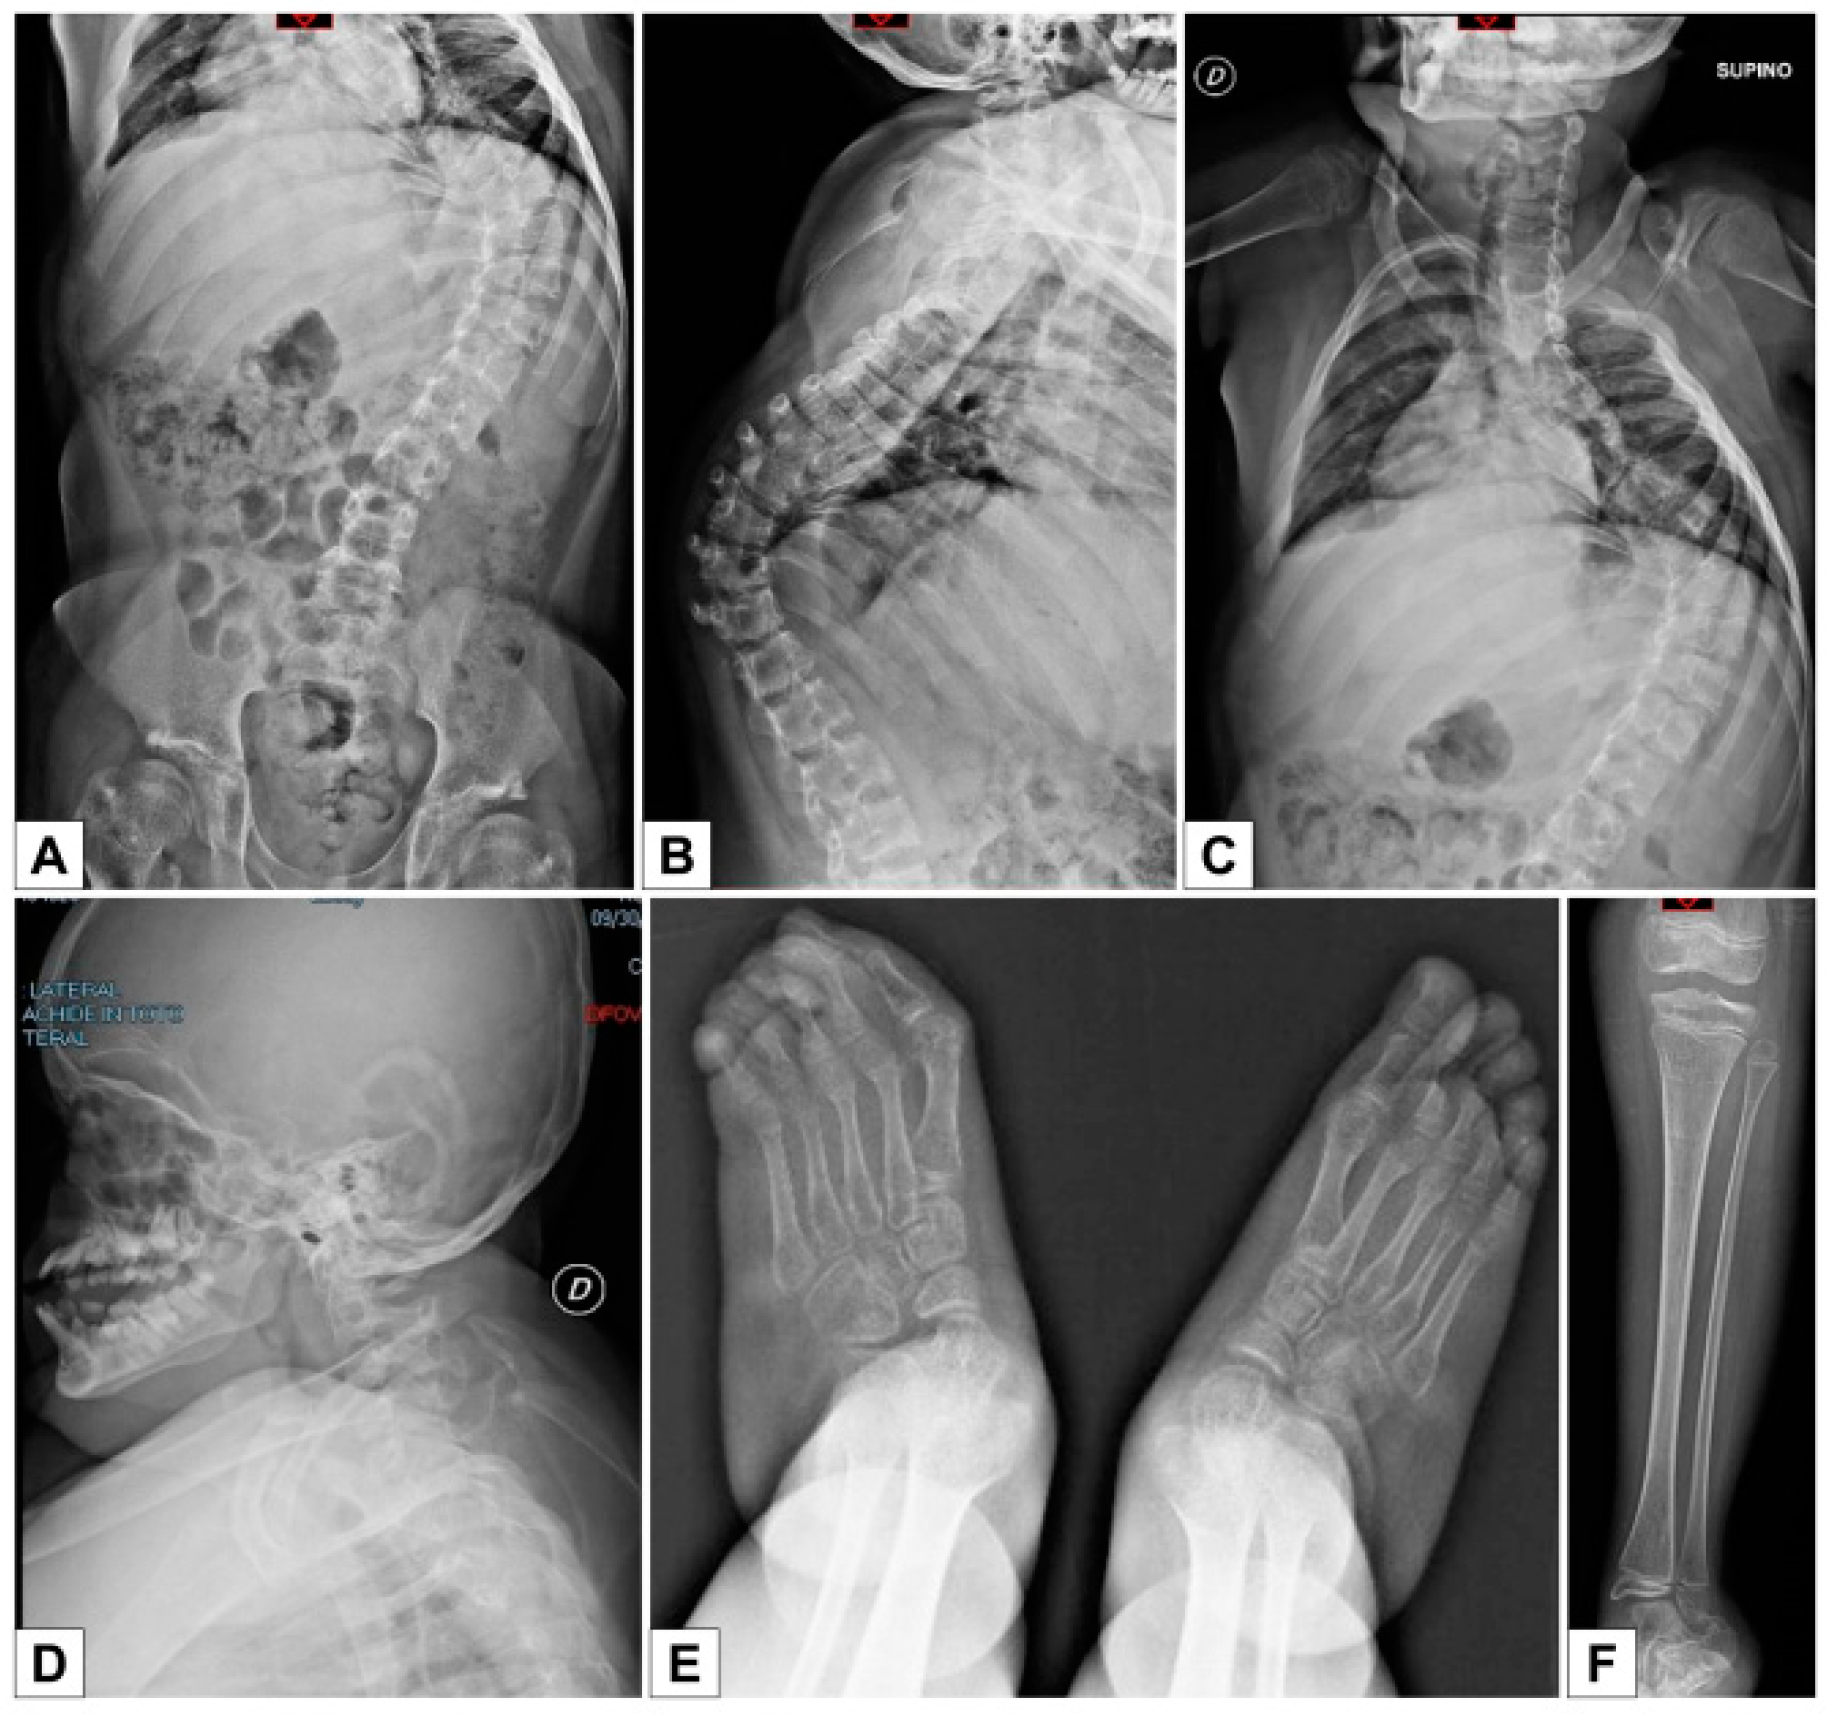

- the extreme distal joint hypermobility and soft, hyperextensible skin, particularly of the hands;

- the radiological signs, which are the main indicator for discriminating spEDS-B4GALT7, associated with radioulnar synostosis, and spEDS-B3GALT6, characterized by kyphoscoliosis (congenital or early onset and progressive) and by the skeletal signs of SEMDJL1 (platyspondyly, short iliac bones, elbow dislocation).